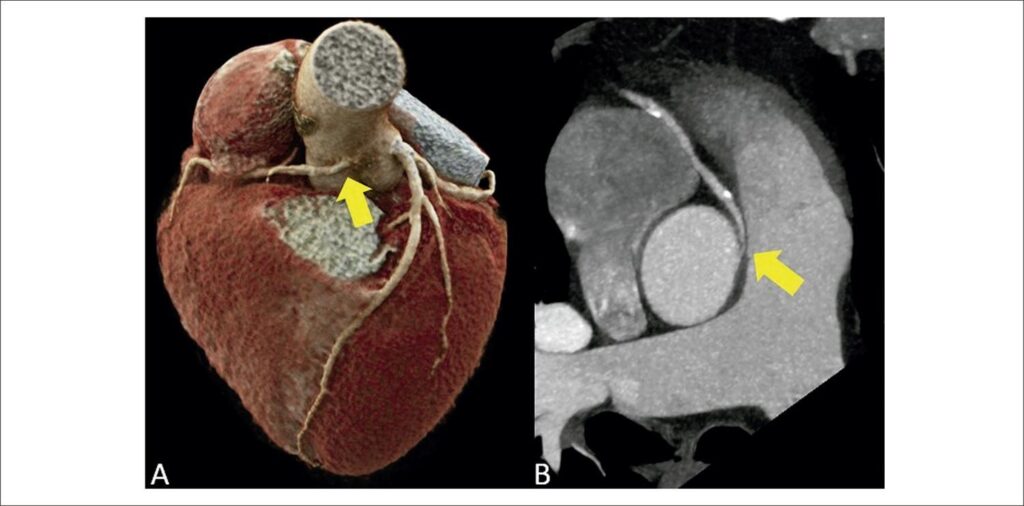

Anomalous origin and course of coronary arteries are rare congenital heart diseases, affecting less than 1% of the general population., Anomalous coronary origin with an interarterial (suprapulmonary) course is characterized by the course of the coronary artery between the ascending aorta and the pulmonary artery trunk, most commonly involving the right coronary artery., Most individuals are asymptomatic, but, among symptomatic patients, chest pain and dyspnea on exertion are the most prevalent complaints. There is also an increase in rates of arrhythmia, sudden death, and acute myocardial infarction., Sudden death is the main complication of this anatomical variant, occurring in approximately 30% of patients.,, In these cases, the narrowing and stretching of the anomalous ostium, mainly during physical exercise and in stressful situations, with consequent reduction in coronary flow, is the substrate for potentially fatal ischemic alterations.,, Since electrocardiogram, in most cases, does not reveal ischemic alterations, diagnosis is generally made through an incidental finding on imaging exams. These exams are of great importance, especially coronary CTA, which, in addition to being a non-invasive exam with high negative predictive value, allows detailed anatomical visualization (angle of the origin, presence of intramural trajectory in the aorta, degree of ostial/proximal luminal reduction) and the correct classification in relation to the pulmonary valve plane (suprapulmonary versus subpulmonary).,,

Recent studies have demonstrated that coronary CTA is an accurate test for identifying myocardial ischemia through FFRCT, when compared to invasive measurement (iFFR) by coronary angiography.,,, The detection of ischemia in coronary CTA is of great importance in decision-making, mainly in plaques considered moderate (50% to 69% luminal reduction) or when there is diagnostic doubt, reducing the number of unnecessary referrals to coronary angiography in cases without ischemia on FFRct.,, Due to the excellent accuracy between the methods in the analysis of a coronary tree without anomaly, the applicability of the method in the context of coronary anomaly has been extrapolated., Our group applied the most current version of a tool for calculating FFRCT currently available only on a research platform developed by Siemens Healthineers (cFRR, version 3.0.0) in the clinical case described. This research tool is available for installation on standard configuration computers, and it uses artificial intelligence tools, with reduced processing time. Currently, commercially available options require the step of sending images in DICOM format for processing in specific centers, with delivery of results at least 24 hours after the images have been sent., The research tool used in this clinical case has advantages, such as fast processing time on standard configuration computers in the analysis room and use of tomographic images from the standard routine protocol, without requiring the addition of a specific protocol or a higher dose of radiation, without the use of stressors., This tool, in general, has some limitations, such as difficulty in defining the coronary borders in the presence of excessive calcification, and the need for high-quality images, without movement artifacts, for adequate automatic detection of the central luminal line and the lines that delimit the coronary borders, allowing adequate calculation of FFRct. It is important to emphasize that this tool distinguishes the interarterial pathways associated with ischemia, considering only the flow obstacle during rest, without estimating the risk of ischemic events associated with dynamic changes secondary to intense exercise. Use of this tool is scarce in the literature, and it still does not have a robust body of evidence. Nevertheless, in the clinical case described, the FFRCT tool was applied in a context different than what is usual, where luminal reduction was not determined by coronary atheromatosis, but by ostial angulation and compression of the proximal segment of the anomalous interarterial pathway. The ischemic response was considered a parameter of poor prognosis; subsequently, the confirmatory invasive functional test (iFFR) was indicated to assist in the therapeutic decision.